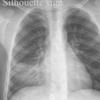

Silhouette sign

RML collapse

Date: 04/29/2014

Views: 4746